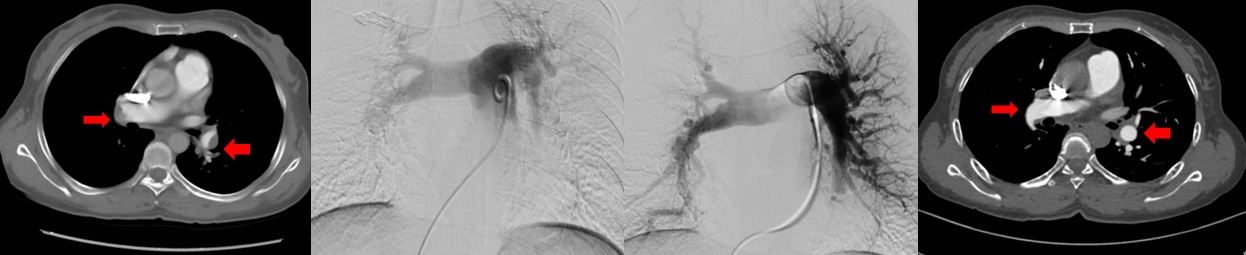

双侧肺动脉基地段狭窄球囊扩张前后对比

北京清华长庚医院血管外科团队在吴巍巍主任的带领下联合麻醉科心内科呼吸科重症医学科等兄弟科室充分评估患者病情明确患者手术指征制定详细的围手术期治疗预案,与患者及家属充分沟通手术的必要性及相关风险后决定采用肺动脉球囊扩张成形术治疗。这是血管外科在静脉血栓栓塞性疾病治疗中的又一次大胆的尝试,无论是医生或是患者均承担了相当大的风险及压力。219日在麻醉科的严密监测下吴巍巍主任、赵俊来医通过右侧股静脉入路选择进入患者左肺动脉基底段狭窄部位,完成肺动脉球囊成形术,球囊扩张后肺动脉形态改善患者术后在监护病房观察一天后顺利返回普通病房,患者恢复顺利。于225再次行右侧肺动脉基底段球囊扩张。患者术后6分钟步行距离明显提高,术后2天即可行走450m,肺动脉力由术前82mmHg降至68mmHg患者顺利出院,由于双侧肺动脉病变广泛,此后还将密切随诊,择期再次行其余部位的肺动脉腔内治疗。